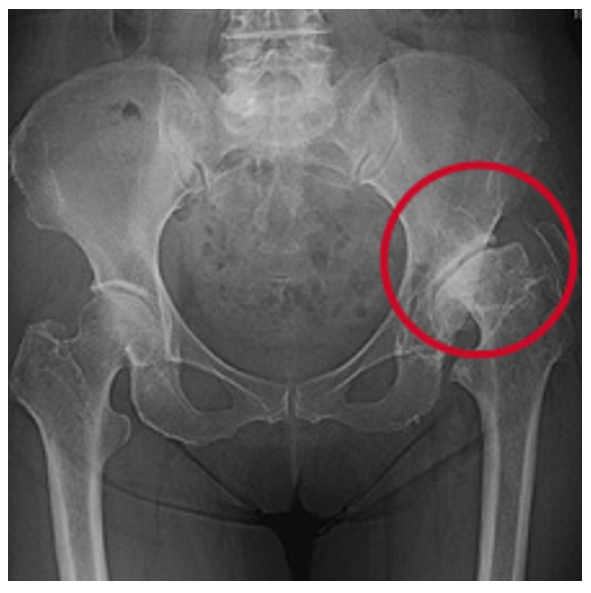

変形性股関節症には、一次性と二次性があります。一次性は、長い年月を経てあるいは関節の使いすぎによって軟骨が消耗して起こります。二次性は、乳児期の股関節の脱臼や発育不全などの臼蓋形成不全によって早期から起こる変形性股関節症です。

レントゲンで見ると一次性は、正常な股関節が長い年月や股関節の使い過ぎによって軟骨が消耗して変形性股関節症が発症します(図7)。二次性は、元々臼蓋形成不全により体重がかかる部分が限られており早期なら軟骨が消耗し変形性股関節症になります(図8)。

図8. 二次性の変形性股関節症

乳児期の股関節の脱臼や股関節の発育が悪いこと(臼蓋形成不全)が原因で起こる。